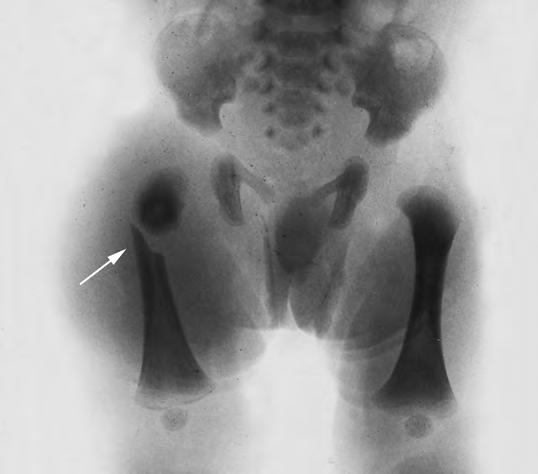

Fractura de fémur

Relativamente frecuente y benigna, ya que no produce acortamiento, no deja secuelas y se consolida con un gran callo.

Puede ser también diafisaria (Fig. 2.29.4) o epifisaria. El desprendimiento epifisario o epifisiolisis superior es confundido a menudo con la luxación congénita de cadera o artritis aguda; una punción articular mostrará la presencia de sangre, o bien será blanca. Debe colocarse un yeso pelvipédico, incluyendo ambas extremidades, para evitar la movilización dolorosa y acelerar el proceso de consolidación en buena posición. También se puede recurrir a la inmovilización de la pierna afecta, en posición vertical, según el método de Schede (suspensión continua). En general, los desprendimientos epifisarios son menos frecuentes que las fracturas, pero llegan a producir mayores secuelas si no se hace una reducción e inmovilización precoces. Suelen presentarse durante partos de nalgas que requieren extracción manual o versión con extracción. Clínicamente se aprecia gran irritabilidad con tumefacción, eritema e hinchazón en la zona afecta, así como impotencia funcional y deformidad de la articulación, típicas de cada localización. Se inicia al segundo día de vida, durando hasta pasada la segunda semana. Radiológicamente sólo se apreciarán los signos de tumefacción de partes blandas, junto a ligeros defectos en la alineación del hueso o espacio articular, ya que inicialmente no existe núcleo de osificación. Su tratamiento requiere reducción precoz e inmovilización, antes que la formación del callo impida la corrección de la epífisis.